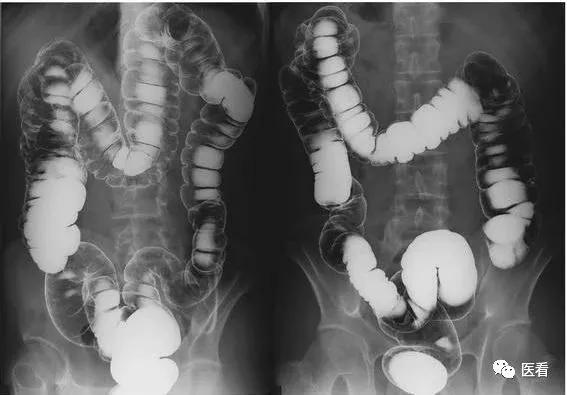

首先让我们来看一张片子

看看胃部,你能看出是什么吗?

这位病人来放射科检查,医生告知她空腹4小时,病人坚决不同意,各种骂街。

结果扫完就这个效果:能看出吃了好大一碗面,一个大胃占了半个肚子,里面塞满了面条。还能看出来病人根本没怎么嚼......

医生各种无奈,根本看不出来什么病。